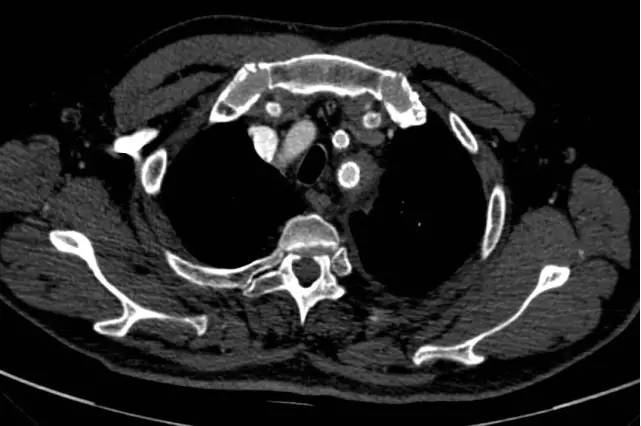

如此凶险的疾病,治疗就是跟时间赛跑。通过CT室开通的绿色通道,20分钟内即完成胸腹主动脉联合CTA检查。结果支持崔文军副主任医师的诊断,但糟糕的是这个病人的主动脉破口紧贴左侧锁骨下动脉,向上累及主动脉弓及升主动脉,向下一直撕裂至双侧髂动脉,右侧肾动脉闭塞,左侧肾动脉真假腔供血,存在急性肾功能衰竭及下肢缺血坏死风险!

左侧锁骨下动脉夹层(白箭头)

近端破口(黄箭头)及周围血肿(红箭头)